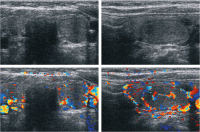

Abbildung 2: Sonographiebefund: Quer- und Längsschnitt durch den rechten Schilddrüsenlappen. Darstellung von echoarmen und zystischen Läsionen, die kleiner als 10 mm im Durchmesser sind.